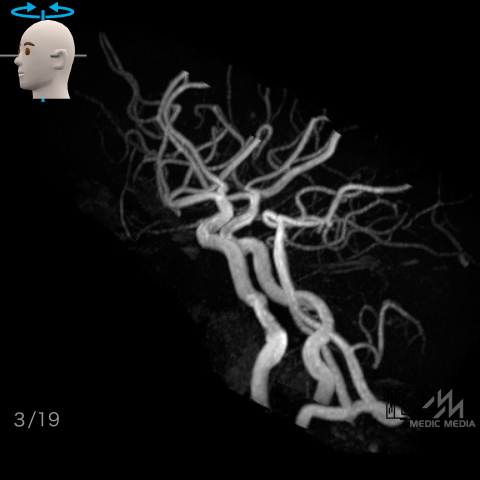

脳動脈(MRA像)

スライド(画像下)を動かし脳動脈の解剖を確認しましょう.

上下軸回転

動脈名表示

動脈名表示+色分け